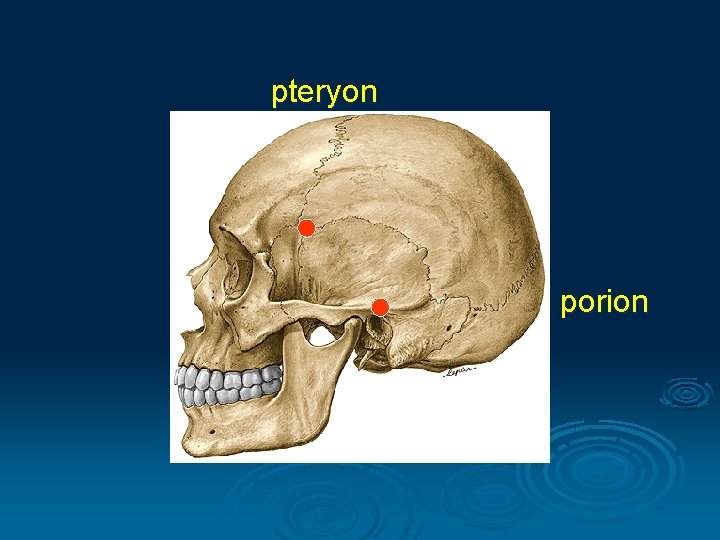

I. Cranimetry Points § Unpaired: nasion, glabella, bregma, akanthion, lambda, orale, opisthocranion, basion, staphylion § Binate: pteryon, porion, euryon, zygion, gonion, endomolare

pteryon porion